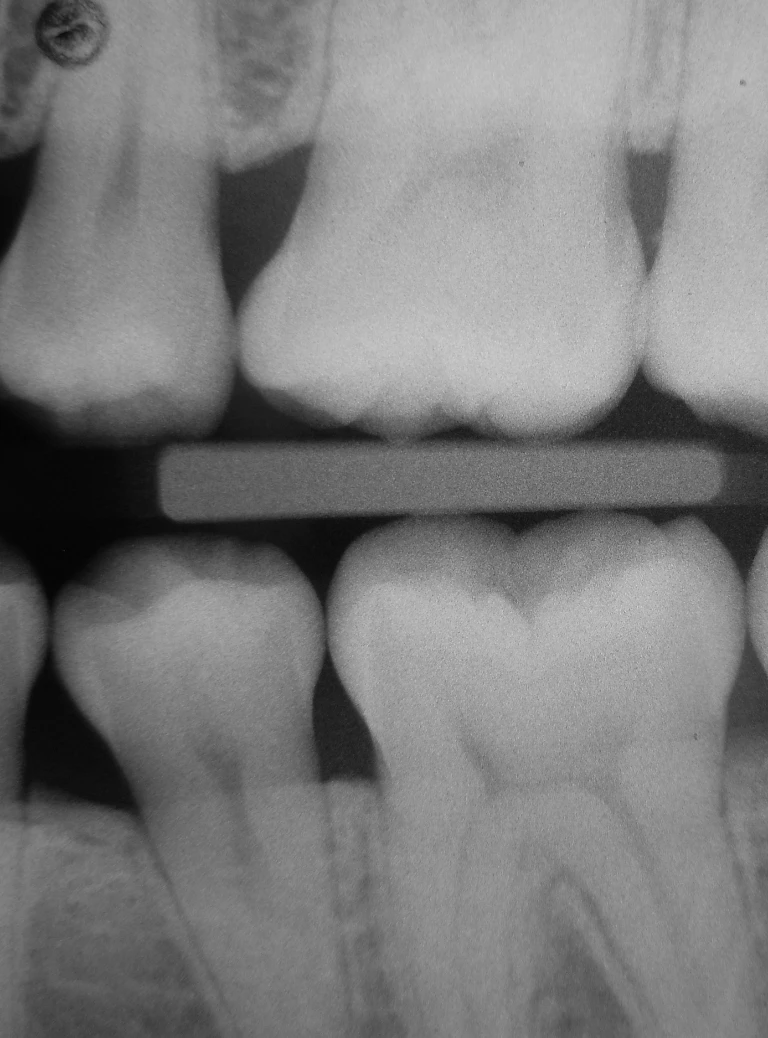

Radiologia stomatologiczna w Bydgoszczy to kluczowy element diagnostyki w stomatologii, pozwalający na dokładną ocenę stanu uzębienia i tkanek otaczających. Wykorzystujemy głównie zdjęcia RTG punktowe, które umożliwiają szczegółowe obejrzenie pojedynczych zębów i wykrycie próchnicy oraz stanów zapalnych. Pantomogram natomiast daje panoramiczny obraz całej jamy ustnej, szczęk i stawów skroniowo-żuchwowych, co jest pomocne w kompleksowej ocenie. Stosujemy nowoczesne cyfrowe technologie, dzięki którym obraz jest wysokiej jakości, a dawka promieniowania minimalna. W gabinecie MałeccyDent w Bydgoszczy dbamy o bezpieczeństwo i komfort pacjentów podczas wykonywania badań radiologicznych.

Zdjęcia punktowe pozwalają na precyzyjną diagnozę i monitorowanie leczenia kanałowego oraz oceny stanu wypełnień. Pantomogram jest często wykorzystywany jako uzupełnienie diagnostyki klinicznej w ocenie zębów i kości szczęk, ułatwiając planowanie leczenia. Każda z metod jest dobierana indywidualnie do potrzeb pacjenta i rodzaju problemu. Radiologia stomatologiczna jest podstawą skutecznego leczenia i monitorowania stanu jamy ustnej.

W stomatologii najczęściej stosujemy zdjęcia punktowe, które dają szczegółowy obraz pojedynczych zębów i okolicznych tkanek. Są one kluczowe w wykrywaniu próchnicy i chorób przyzębia oraz w monitorowaniu leczenia kanałowego. Pantomogram to zdjęcie panoramiczne, które pokazuje całe uzębienie, kości szczęk i stawy skroniowo-żuchwowe, co jest pomocne w diagnozie ogólnej. Metody te zapewniają wysoką rozdzielczość i minimalną dawkę promieniowania. W MałeccyDent w Bydgoszczy korzystamy z nowoczesnych aparatów cyfrowych, które gwarantują bezpieczeństwo i precyzję diagnostyki.

Zdjęcia punktowe wykrywają próchnicę i zapalenia tkanek okołozębowych.

Pantomogram pokazuje panoramiczny obraz zębów oraz struktur kości szczęk i żuchwy.